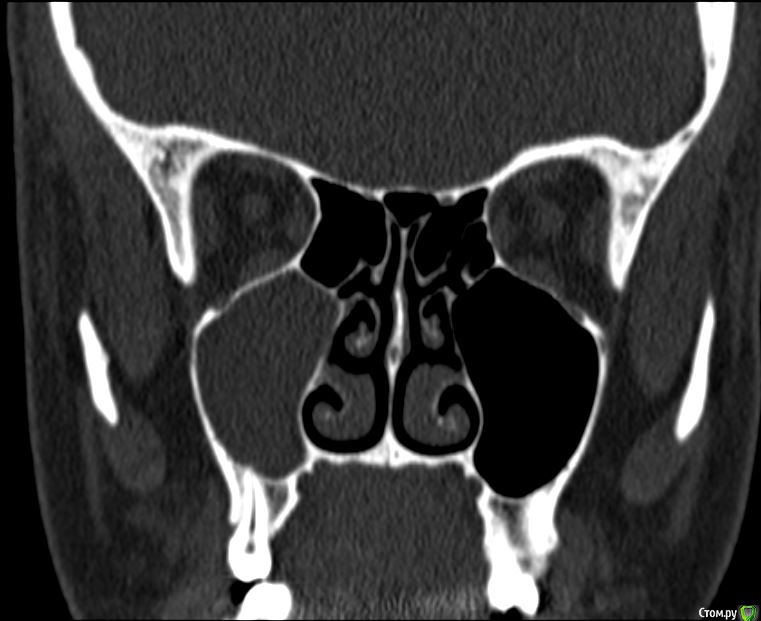

Лисица Опубликовано 26 июля, 2015 Автор Поделиться Опубликовано 26 июля, 2015 (изменено) Вы же не думаете, что Вам назначат а/б терапию по интернету? Я просто не знаю, исходя из каких показателей она назначается. Поэтому осведомилась на всякий случай. Итак, сходила я сегодня на КТ. И по ходу мне сделали что-то не то... Когда я обратилась в клинику, я уточнила, что мне нужно КТ для эндодонтии, чтобы видно было каналы, с достаточным разрешением, чтобы было видно зубы и их корни, входящие в верхнечелюстной синус. Администратор клиники уточнила у врача и сказала, что мне нужно заказывать не КТ верхней челюсти, а КТ пазух. У рентгенолога я также повторила все описанное, рассказала, что при лечении каналов вчера была продырявлена пазуха, уточнила, будут ли видны как следует зубы и их каналы, меня заверили, что "все будет". Причем у врача, судя по описанию на сайте клиники, была ординатура по хирургии в медико-стоматологическом университете, так что он, уж наверное, понимал, что мне нужно. В итоге я получила пленку со снимками формата чуть ли не А3 и диск. На пленке все зубы были просто белыми и коронки видны не целиком. Заключение: в правой верхнечелюстной пазухе уровень жидкости, острый правосторонний гайморит.Думала, может в программе можно будет увеличить разрешение. Но похоже, что нет... или я просто ламер? Зубы просто размытые и белые... Прилагаю сделанные мной скриншоты, как мне кажется, наиболее показательные... Если нужно другие "виды", то скажите какие, или такие снимки вообще ни о чем? Программа просмотра называется Philips DICOM Viewer R3.0-SP03. Аппарат был не местный "на голову", а здоровый, куда заезжаешь в лежачем положении. Изменено 26 июля, 2015 пользователем Лисица Ссылка на комментарий

St. Опубликовано 27 июля, 2015 Поделиться Опубликовано 27 июля, 2015 Гайморит справа есть, и жидкость тоже. Корни этого зуба действительно заканчиваются в гайморовой.Ничего такого страшного, чтоб однозначно удалять зуб я не вижу. С гайморитом - к лорам на лечение.В зубе я бы ещё раз поменяла лекарство на пару недель, пока гайморит не притихнет, потом постоянно пломбировать. 1 Ссылка на комментарий

Лисица Опубликовано 27 июля, 2015 Автор Поделиться Опубликовано 27 июля, 2015 St., большое спасибо за ответ! Моя врач планировала закрыть его в среду (зная о том, что пазуха проткнута). Если запломбировать, пока воспаление есть, какие могут быть проблемы? И еще она сказала, что нащупала 4-й тонкий канал, но не было времени его прочистить, так что она оставила как есть до среды. Сказала, что почистит и сразу же закроет. Судя по КТ, корня 3, значит в одном из них 2 канала? В 3D похоже, что корни с медиальной стороны сросшиеся какие-то... и на небном тоже борозда. Ссылка на комментарий